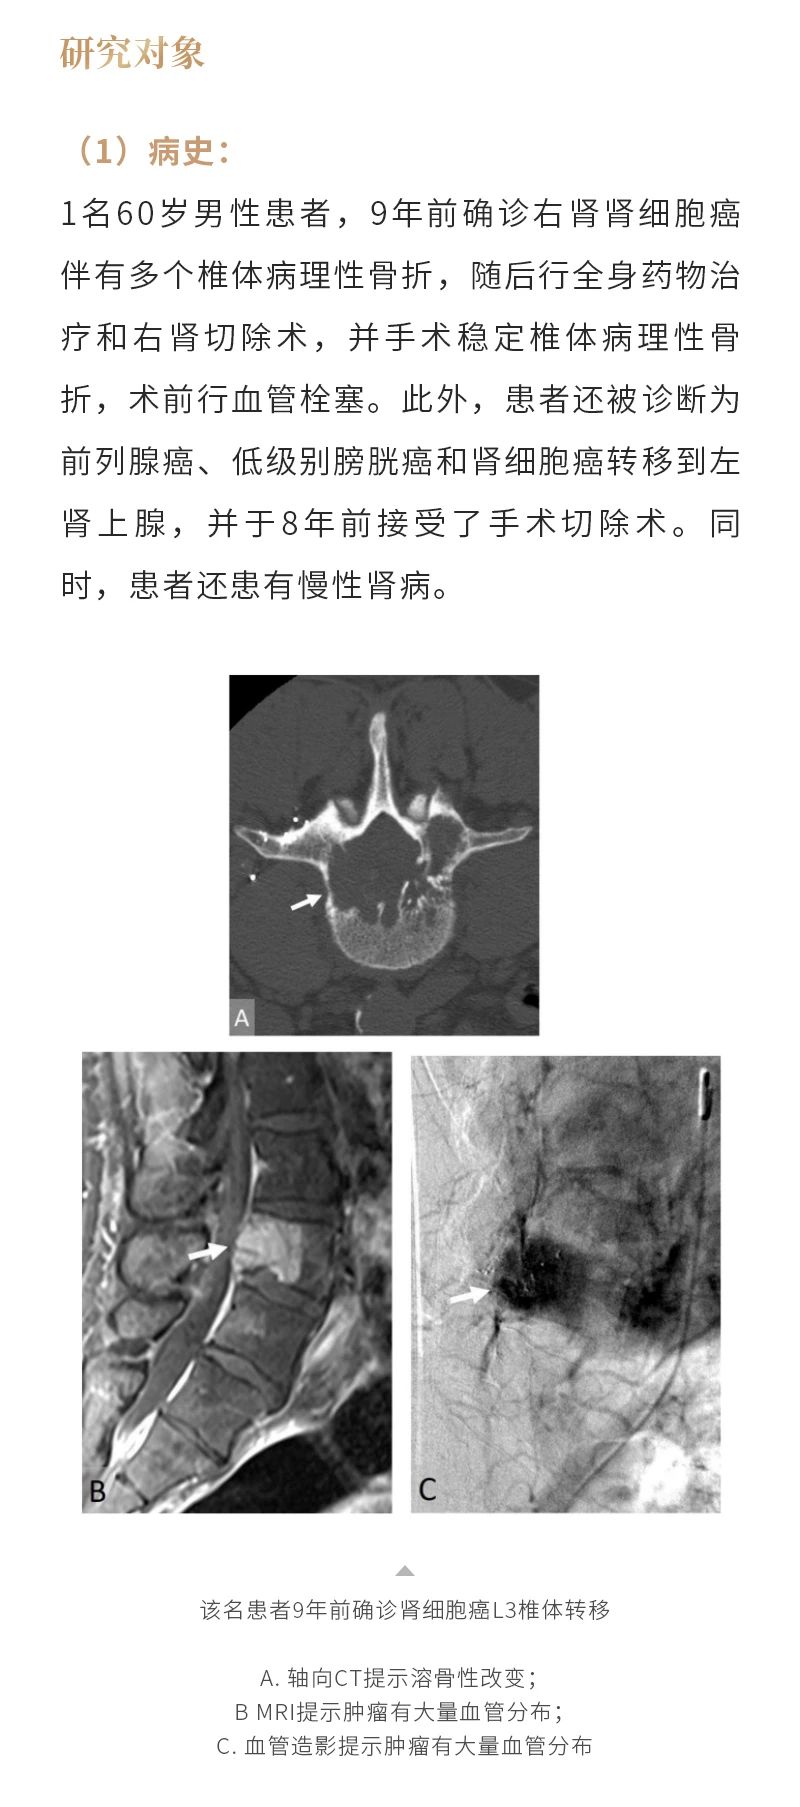

冷凍消融骨腫瘤——【海杰亞科研資訊】第285期

發(fā)布時間:2024-10-18 | 作者:海杰亞 | 瀏覽次數(shù):1108